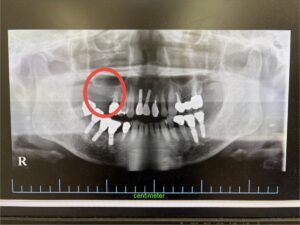

また、歯科医院での定期的な検診も忘れないでください。目に見える症状がないからといって、歯の健康が完全だとは限りません。プロの目で確認することで、初期の虫歯や歯周病を早期に発見し、治療が必要な場合には早めに対応できます。定期的なクリーニングも、普段のケアでは取り切れない汚れをしっかりと除去し、歯を健康に保つのに役立ちます。